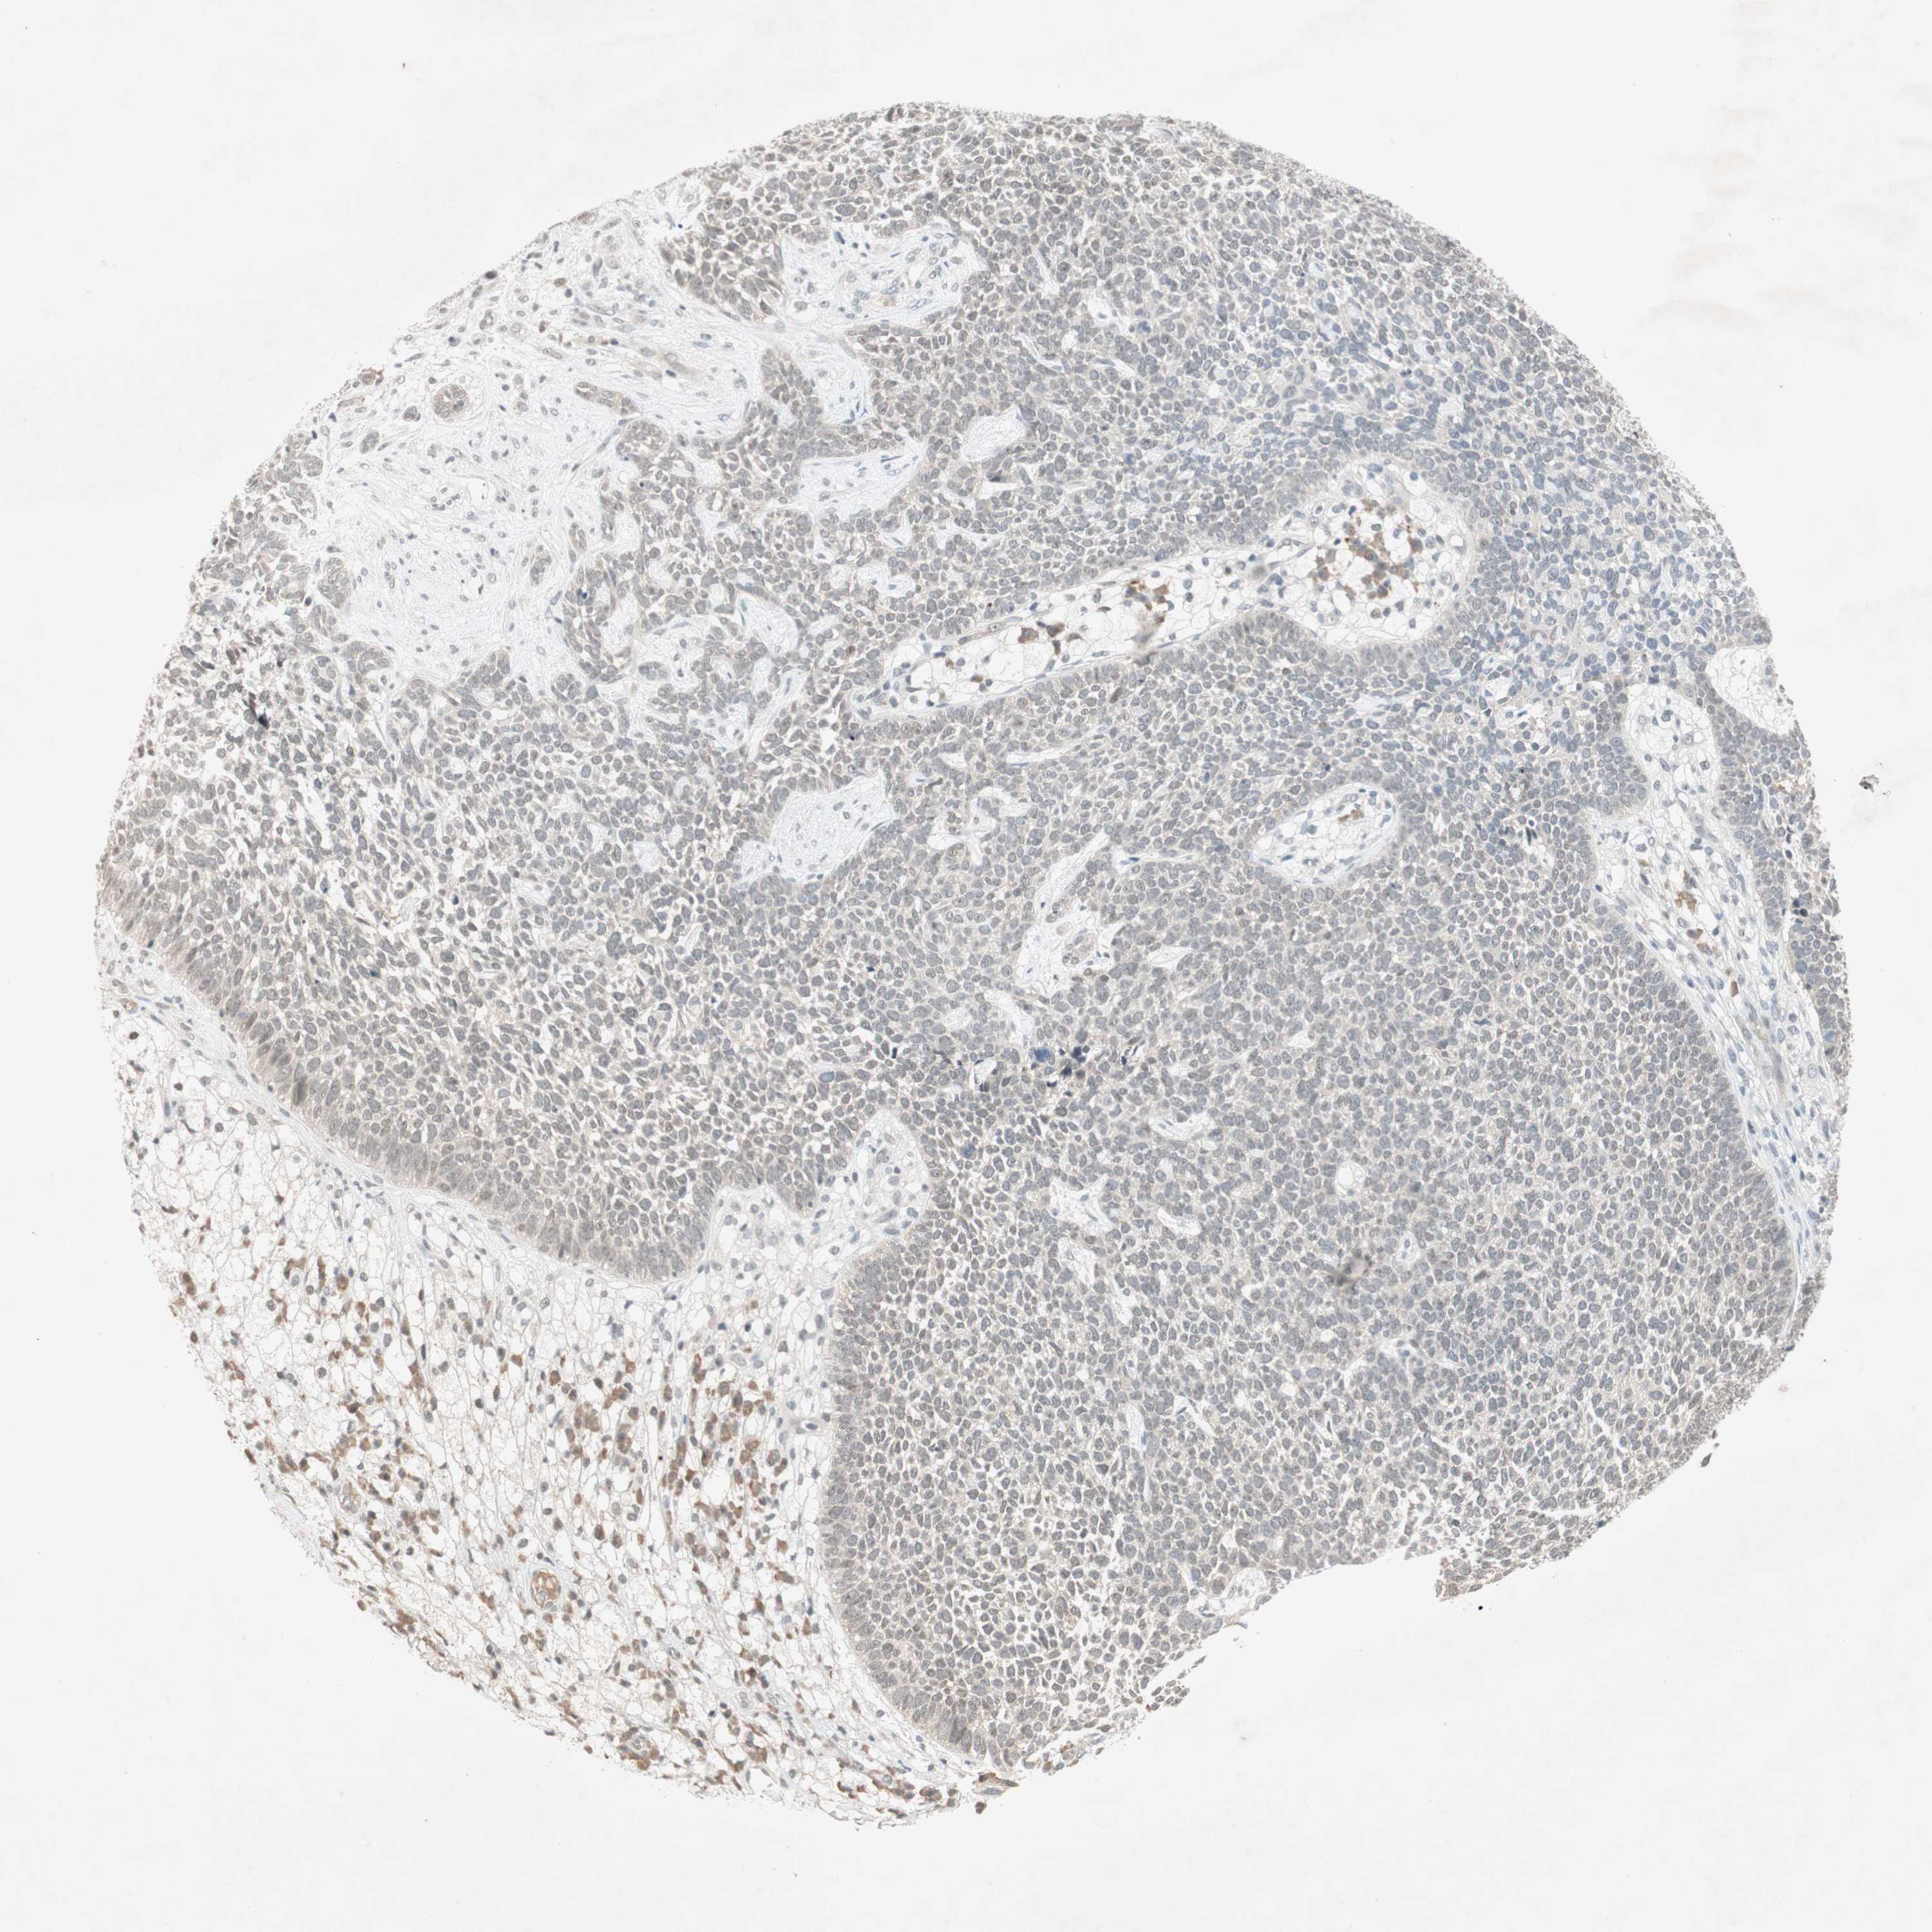

SKIN CANCER - Protein expressioni

A mouse-over function shows sample information and annotation data. Click on an image to view it in a full screen mode. Samples can be filtered based on level of antibody staining by selecting one or several of the following categories: high, medium, low and not detected. The assay and annotation is described here.

Antibody stainingi

Antibody staining in the annotated cell types in the current human tissue is reported as not detected, low, medium, or high, based on conventional immunohistochemistry profiling in selected tissues. This score is based on the combination of the staining intensity and fraction of stained cells.

Each image is clickable and will lead to virtual microscopy that enables deeper exploration of all samples and also displays staining intensity scores, fraction scores and subcellular localization as well as patient and tissue information for each sample.

Antibody HPA003750

Staining

High

Medium

Low

Not detected

Intensity

Strong

Moderate

Weak

Negative

Quantity

>75%

75%-25%

<25%

None

Location

Nuclear

Cytoplasmic/membranous

Cytoplasmic/membranous,nuclear

Squamous cell carcinoma, NOS

Squamous cell carcinoma, metastatic, NOS

Basal cell carcinoma

Papilloma, NOS